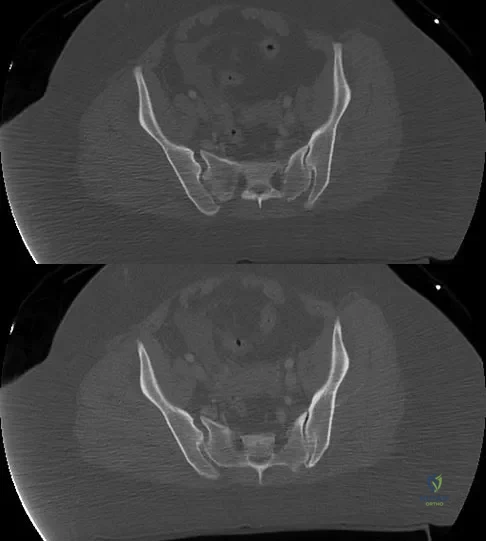

A 36-year-old woman was injured in a train derailment. She has a significant open depressed skull fracture with active bleeding, a hemopneumothorax, and blood in the left upper quadrant and colic gutter by Focused Assessment with Sonography for Trauma (FAST) examination. Additionally, she has the pelvic injury seen on the CT scans in Figures 18a and 18b. The mortality rate for this patient approaches

Explanation